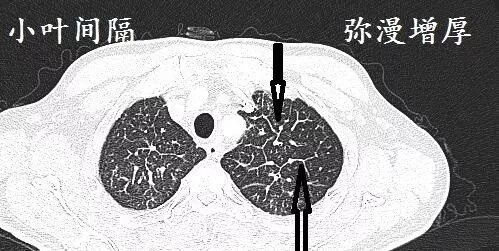

上图是什么?

接着看另一个层面。

弥漫小叶间隔增厚,肿块,很多是肺癌。哪种肺癌?很多是肺腺癌。这就是肺腺癌引起的癌性淋巴管炎